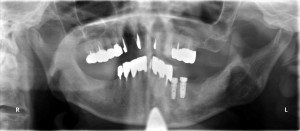

術後のパノラマです。